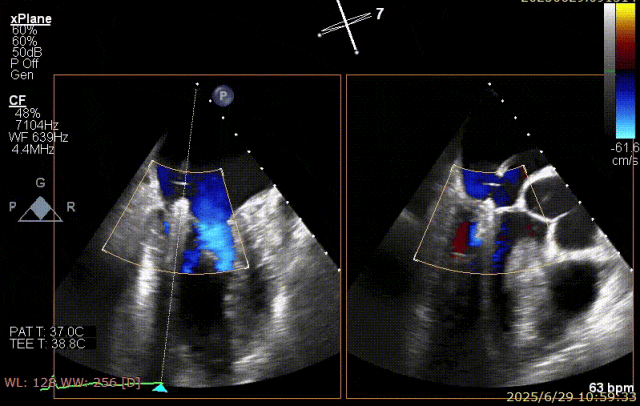

术前超声

患者术前 TEE 可见 P3 区脱垂二尖瓣环前后径(AP)约 37 mm,CC 径约 41 mm,瓣叶无明显钙化及裂隙,后瓣瓣尖探及一长约 9 mm 短带样回声漂附,二尖瓣口面积约 5.3 cm²。

经我院心脏超声检查提示:左房室增大伴二尖瓣后瓣脱垂(P3 区,腱索断裂)并重度关闭不全(Carpentier IIb 型,反流分级 4+);符合高血压性心脏病改变;少至中等量心包积液;左室舒张功能降低,收缩功能测定在正常范围并呈假性高排表现。